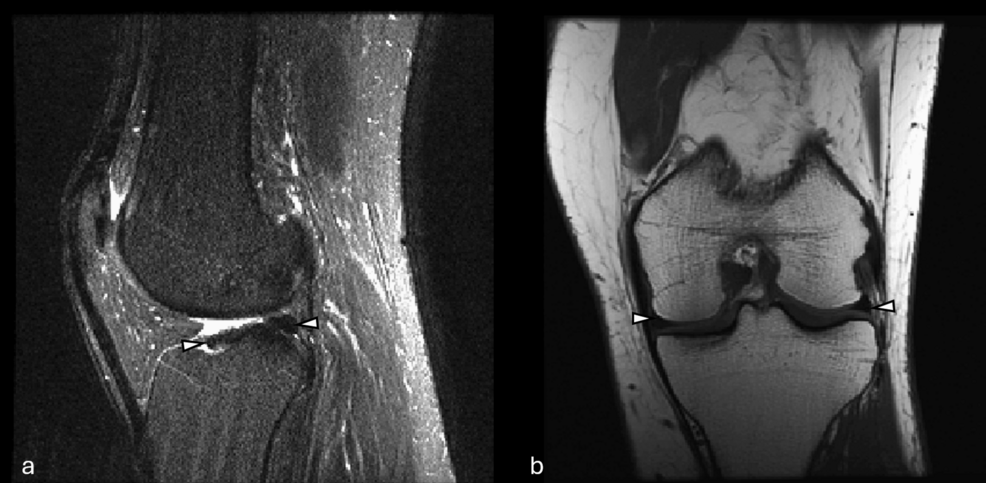

Nearly 3 million knee arthroscopies are performed annually in the US, many for suspected meniscal tears. But a significant percentage – estimates range from 20-40% – show no actual tear upon closer examination. This diagnostic uncertainty leads to unnecessary procedures, patient discomfort, and substantial healthcare costs. Now, a new pilot study exploring the capabilities of Generative Pre-trained Transformer 5 (GPT-5) as a multimodal large language model is suggesting a future where AI dramatically improves the accuracy and speed of meniscal tear detection on knee Magnetic Resonance Imaging (MRI), potentially reshaping orthopedic care as we know it.

Traditional MRI analysis relies heavily on the expertise of radiologists and orthopedic surgeons. While highly skilled, human interpretation is susceptible to subjectivity and fatigue. The study, published in Cureus, demonstrates that GPT-5, when combined with image analysis, can achieve promising results in identifying meniscal tears. This isn’t simply image recognition; it’s about the AI understanding the *context* of the image, integrating visual data with textual information from patient history and clinical notes – a key characteristic of multimodal LLMs.

Previous AI models focused primarily on image analysis. GPT-5, however, leverages its vast language processing capabilities to interpret not only the MRI scan but also the accompanying clinical data. This allows it to build a more comprehensive understanding of the patient’s condition. This capability is fueled by advancements in visual-linguistic pre-training, allowing the model to connect visual features with descriptive language.